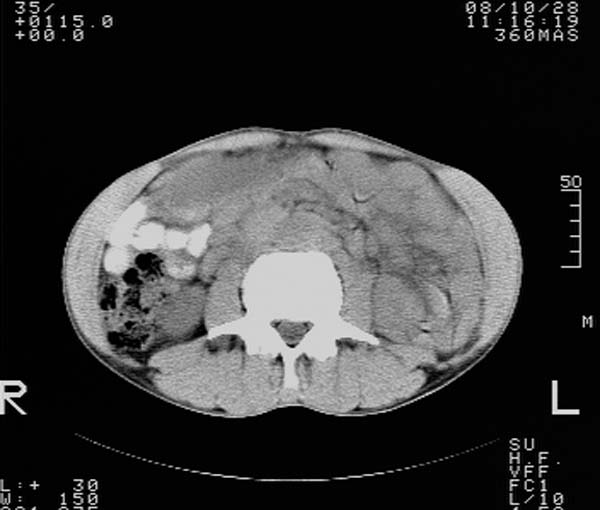

m,65y。半年前发现颈小结节,逐渐增多增大,现双侧耳后、颌下及颈部表浅淋巴肿大。胸片示双肺门增大。外院曾穿刺诊断为淋巴结核。在我科作胸腹部ct,我们觉得外院病检有误。现将图像上传请战友讨论。

纵隔内及腹膜后广泛淋巴结肿大,脾大,肝内似可见低密度影,结合病史半年前发现颈小结节,逐渐增多增大,现双侧耳后、颌下及颈部表浅淋巴肿大。考虑淋巴瘤。

我们也是首先考虑淋巴瘤。只是外院病检报告是结核。让人迷惑。肝左叶多发低密度占位,没增强不好定论。

纵隔,双肺门腹膜后多发淋巴结重大,非融合,肝脾轻度肿大,双肺野弥漫性小结节;考虑淋巴瘤,结节病可能性

纵隔内,双肺门、腋窝及腹膜后多发肿大淋巴结影,肺内小结节影,肝脾体积增大,支持淋巴瘤。肝内多发低密度影,考虑小囊肿。

考虑淋巴瘤肺、肝内转移,脾脏肿大。

纵隔内,双肺门、腹膜后多发肿大淋巴结影及颈部淋巴结肿大,肝脾体积大.结合临床,淋巴瘤可能性大。